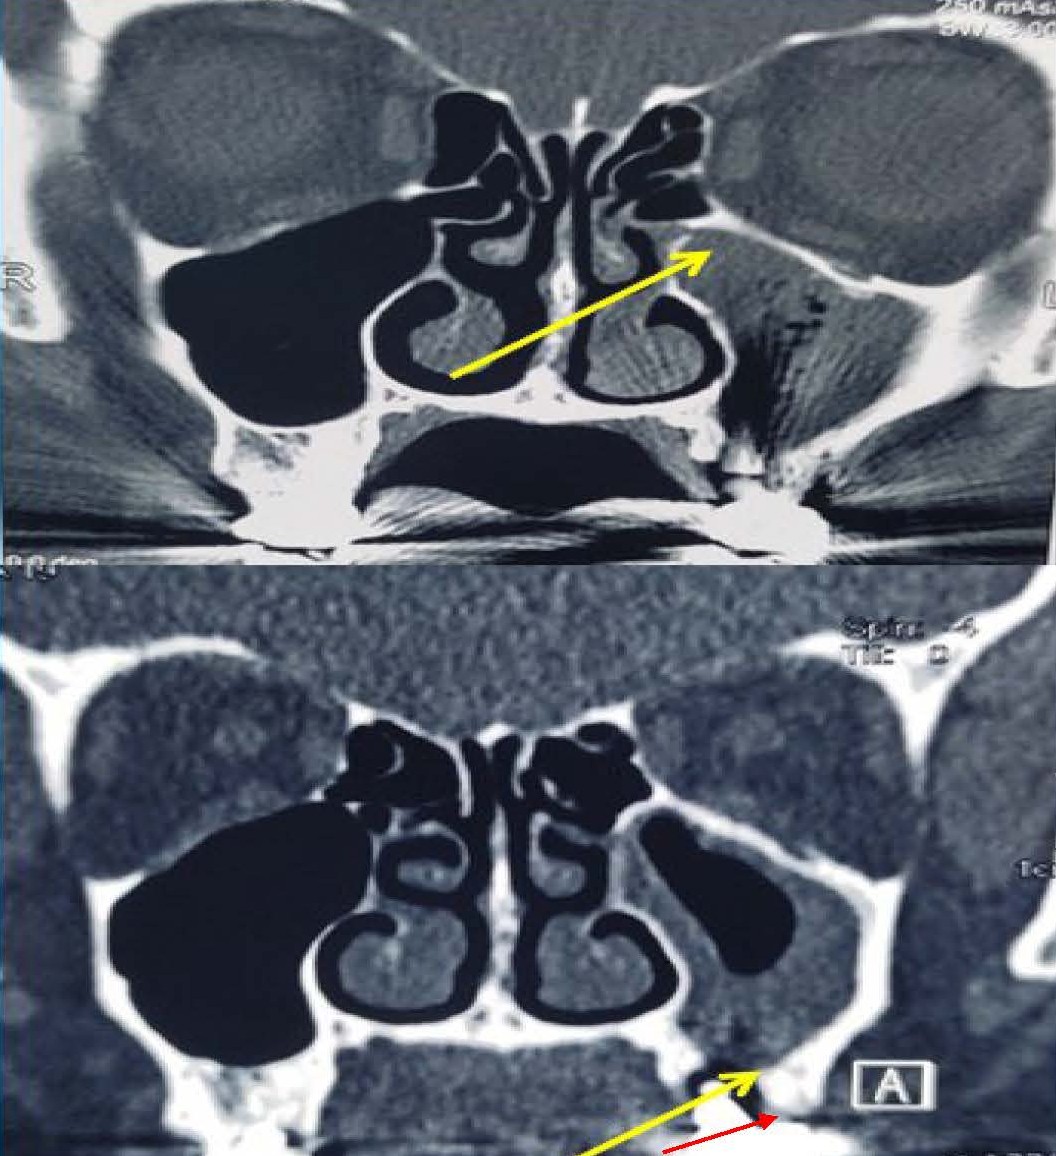

A 71 year-old lady reported to the ENT OPD with complaints of post nasal drip and foul-tasting discharge in her mouth around her left upper last teeth for the past one year. She had received dental implants (Titanium Alloy Grade 5 Endosteal implants) two years ago in her upper left jaw, last two teeth (molars). There was no history of pain, bleeding, swelling, any eye symptoms, loosening of implants or frank pus discharge from gums or nose. On examination there was no swelling in or around cheek or eye or gums; local examination revealed no obvious opening around the dental implant, but on blowing patient felt an air leak. Remaining ENT examination was within normal limits. A diagnostic nasal endoscopy revealed some degree of right-sided deviated nasal septum; rest examination was unremarkable. A contrast-enhanced CT scan of nose and paranasal sinuses revealed mucosal thickening in the left maxillary and anterior ethmoidal sinuses (Figure 1). We obtained CT as CBCT was not available in our institution. No obvious sinus track could be visualized. The right side sinuses were normal. There was no history of hypertension/diabetes mellitus/any other chronic illness or medications. Dental opinion was sought and local infection/periodontitis/implant infection were ruled out.

Figure 1. Upper panel showing CT image with arrow pointing to left maxillary sinus opacification, suggestive of odontogenic maxillary sinusitis. Lower panel: yellow arrow pointing to rarefaction. Red arrow pointing to presumptive area of breach i.e. possible site of oroantral fistula or leak.